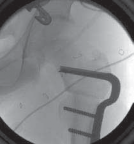

19. The seating chisel must be inserted perpendicular to the long axis of the femur if derotation is the only objective (

TECH FIG 2C

). Any deviation from the perpendicular on the AP view will lead to varus or valgus changes in the neck–shaft axis.

20. The face of the seating chisel should also be perpendicular to the long axis (in the sagittal plane) to prevent unintended flexion or extension through the osteotomy (

TECH FIG 2D

).

--- TECH FIG 2 • Intraoperative C-arm–guided insertion of the seating chisel for the blade plate.A. Insertion of the guide pin in the superior part of the neck at right angles to the long axis of the femur. B. Position of the guide pin along the midfemoral neck axis in the frog-leg lateral view. C. Position of the seating chisel parallel to the guide pin and perpendicular to the long axis of the femur. D. Position of the seating chisel parallel to the guide pin and along the midfemoral neck axis on the frog-leg lateral view. E. The seating chisel is backed out from its final position to disimpact the chisel before the osteotomy.Pr FiAE